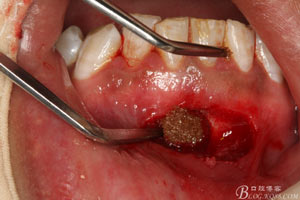

圖8.超聲骨刀去除根尖周圍感染骨質(zhì)

圖9.清晰可見牙膠從31根尖1/3溢出。

圖16. 缺損骨腔填塞一枚膠質(zhì)銀